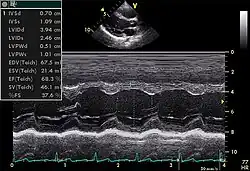

Échocardiogramme normal.

Le cœur est un organe tridimensionnel mobile. La prise en compte de cette quatrième dimension (le temps) est nécessaire pour une bonne appréhension de l'organe dans sa globalité. Cela nécessite une résolution temporelle suffisante pouvant être caractérisée par la cadence d'acquisition des images : elle doit être au moins d'une vingtaine images/s et idéalement supérieure à 50 images/s (pour permettre une visualisation correcte en ralenti, surtout si la fréquence cardiaque est élevée). De même, l'analyse à l'aide d'une image, par essence, bidimensionnelle, d'un organe quadridimensionnel, impose certains artifices : c'est le mode Tm (pour l' anglais : time motion), utilisé de manière courante, avec en abscisse le déroulement du temps et en ordonnée les échos détectés sur une seule ligne de tir.